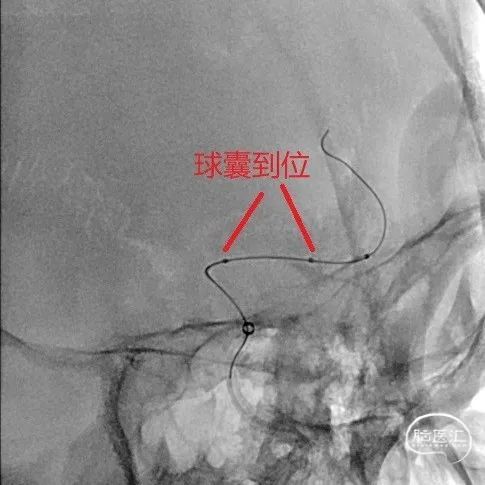

经6F中间导管,微导丝到位后引导Fastunnel®输送型球囊扩张导管到位至左侧大脑中动脉狭窄部位。

Fastunnel®输送型球囊扩张导管打压成形扩张狭窄病变部位,压力8atm,随后造影可见成形满意。